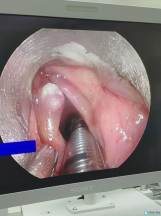

阿里地区人民医院耳鼻喉科开展首例 支撑喉镜下声带息肉切除术

阿里地区人民医院耳鼻喉科开展首例 支撑喉镜下声带息肉切除术

阿里地区人民医院耳鼻喉科开展首例 支撑喉镜下声带息肉切除术 近日,在援藏老师的带领下,阿里地区人民医院耳鼻喉科顺利完成了首例支撑喉镜下声带息肉切除术,手术疗效确切,术...